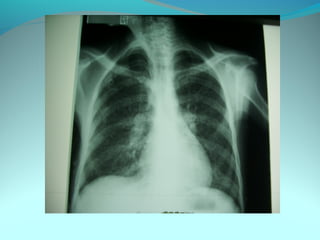

Opacité latéro_trachiale et hilaire droite grossierement arrondie de

6cm de diam dense et homogene

 la limite interne se confend avec le mediastin et la limite externe

nette convexe vers le mediastin

elle confond avec le mediastin évoquant une image mediastinale

Par ailleur on note:

Une surrélevation de la coupole diaph

Un coblement …..

DIAGNOSTIC:

Lymphome H ou NH

Volumineuse ADP tuberculeuse ou sarcoidosique